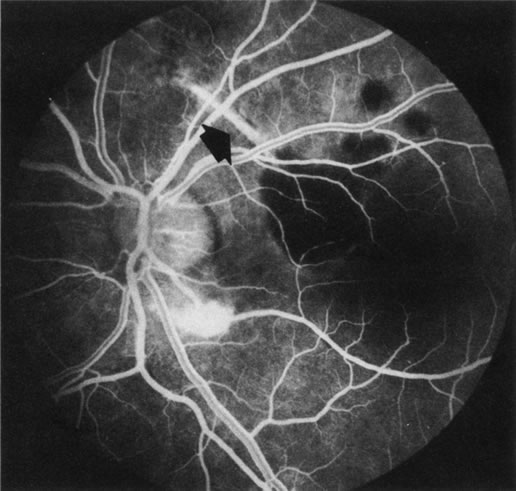

Fig. 3. Notched retinal pigment epithelium (RPE) detachment. There is a notch at the superotemporal border of a large RPE detachment that fills unevenly with fluorescein (large arrowhead). There is also a superior neovascular complex (small arrowhead) that hyperfluoresces. (Courtesy of Dr. Kenneth G. Noble.)